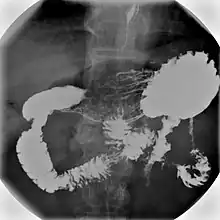

Enteroclysis in double contrast technique showing stenosis of the small intestine

• Enteroclysis, also called small bowel enema, is a barium X-ray examination used to display individual loops of the small intestine by intubating the jejunum and administering barium sulfate followed by methylcellulose or air.[5]

In addition to fasting for 8 hours prior to examination, a laxative may also be necessary for bowel preparation and cleansing.[12] The main aim of this study is to distend the proximal bowel through infusion of large amount of barium suspension. Otherwise, the distension of distal small bowel is generally similar with small bowel follow-through. Therefore, there is a need to pass a tube through the nose into the jejunum (nasojejunal tube) to administer large amount of contrast. This can be unpleasant to the subject, requires more staff, longer procedural time, and higher radiation dose when compared to small bowel follow-through. The indications for enteroclysis are generally similar to small bowel follow-through. Barium suspensions such as diluted E-Z Paque 70% and Baritop 100% can be used. After that, 600 ml of 0.5% methylcellulose is administered after 500 ml of 70% barium suspension is given. Bilbao-Dotter tube and Silk tube can be used to administer barium suspension. The subject should be fasted overnight, any antispasmodic drugs should be stopped one day before the examination, and Tetracaine lozenges can be used 30 minutes before the procedure to numb the throat for nasojejunal tube insertion.[13]

The filling of the small intestines can be viewed continuously using fluoroscopy, or viewed as standard radiographs taken at frequent intervals. The technique is a double-contrast procedure that allows detailed imaging of the entire small intestine. However, the procedure may take 6 hours or longer to complete and is quite uncomfortable to undergo.[23]

• Enteroclysis has shown to be very accurate in diagnosing small bowel diseases, with a sensitivity of 93.1% and specificity of 96.9%. It permits detection of lesion which may not be seen with other imaging techniques.[7] There is no significant difference in terms of detection of clinically significant findings, sensitivity or specificity between enteroclysis and CT enterography.[1] Enteroclysis compares favorably with wireless capsule endoscopy and double-balloon endoscopy in the diagnosis of mucosal abnormalities of the small bowel.[24]